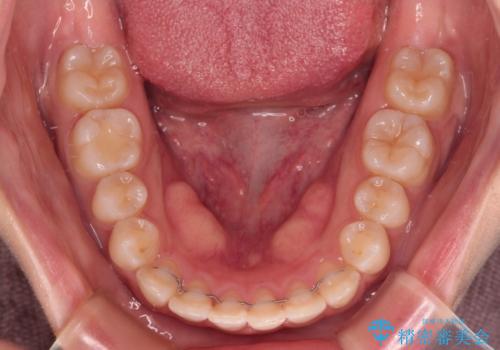

当初予定通り、1年で治療を終えることができました。

後戻り防止はマウスピースで行うため、急に自己管理が必要となるため、移動の最後をマウスピース矯正で行うことで、マウスピース非装着による後戻りリスクを回避する工夫をしています。